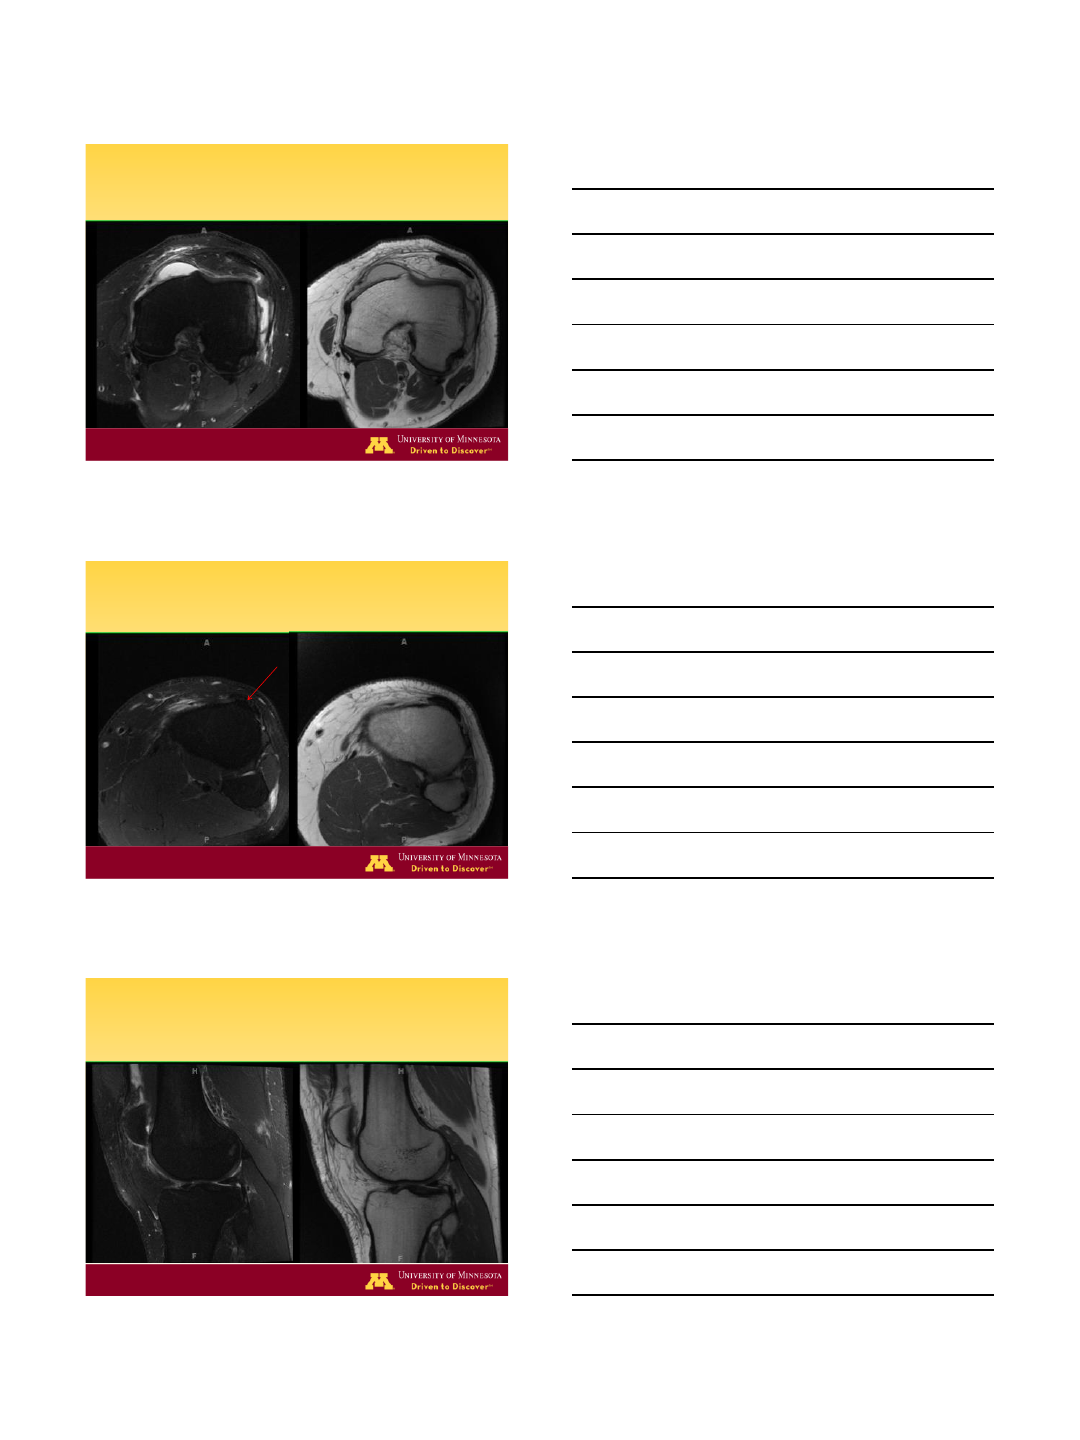

MRI –ACL Tear

MRI –Lateral Meniscus Tear

MRI –Chondral Defect/Loose Body

ACL: Complete Tear

Primary signs

•edematous mass

• “empty notch”

•irregular, horiz contour

•focal disruption